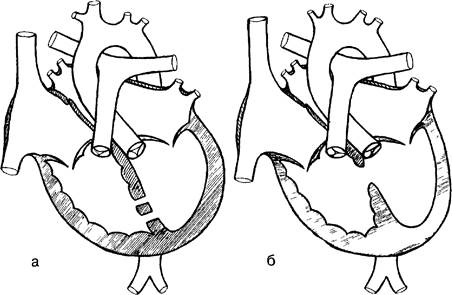

Рис. 3. Схема сердца с дефектом межжелудочковой перегородки. (а — ДМЖП в мышечной части; б — ДМЖП перимембранозный).